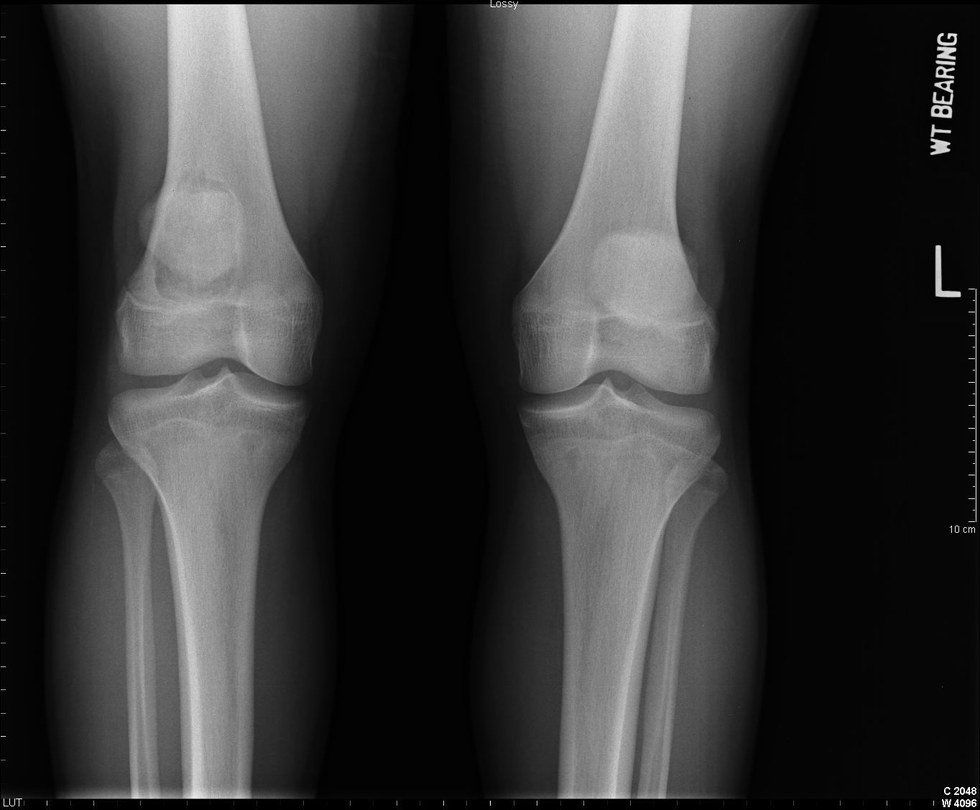

Back at the doctors, I was told to go to a knee specialist, still not knowing what was wrong with me. After waiting a couple of months to see the recommended knee specialist, I finally found out what was wrong with me. I had dislocated my knee cap and torn my patella ligament-- torn the ligament that held my knee cap in place. I was told I had two choices. The first, get surgery. The second, wait to see if it will repair its self. I chose the second option.